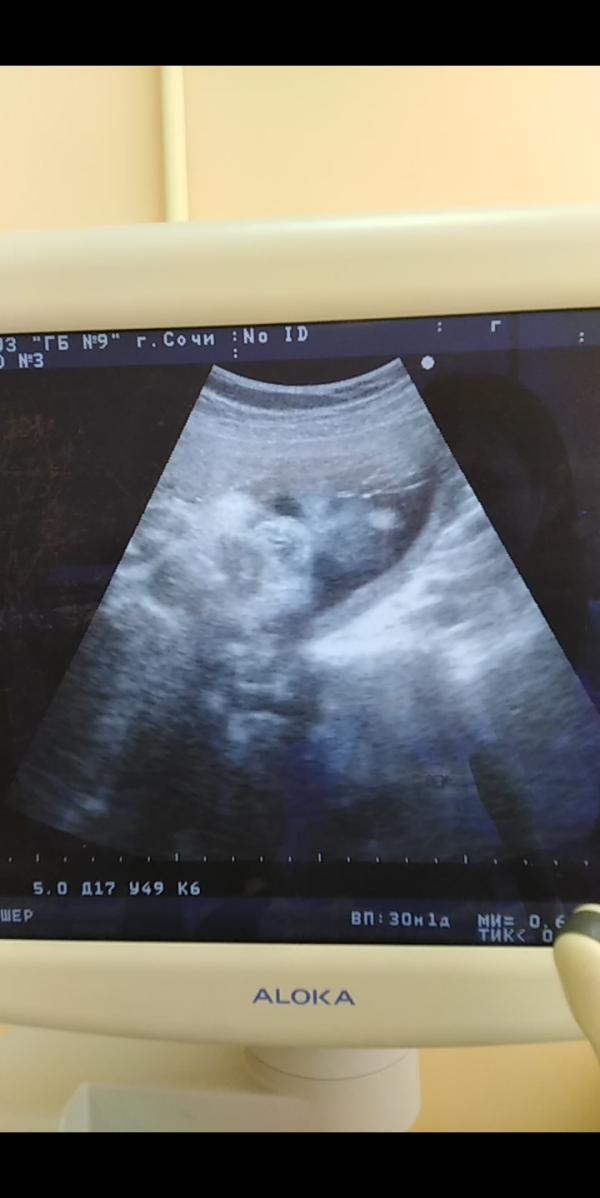

Вчера бвли на 3м УЗИ

Мы весим уже 1,6 кг

Лежим головкой вниз и у нас 1 обвитие